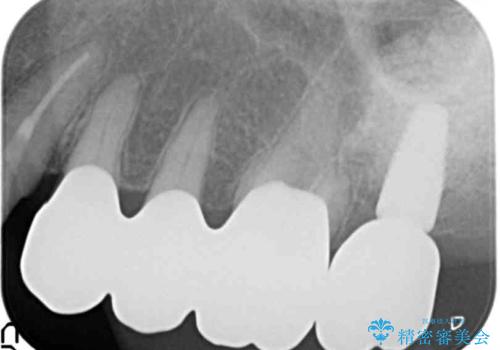

歯ぎしりに抵抗する歯周補綴 インプラント補綴

- 61万円(仮歯・フルジルコニアクラウン×4 ・インプラント・チタンカスタムアバットメント )費用は治療当時の料金となります

分岐部病変を併発していた歯は、抜歯としインプラントによる咬合機能の回復。残すことのできる歯は歯周治療後連結補綴を行い歯ぎしりに対抗します。

夜間のナイトガード装着は必須です。